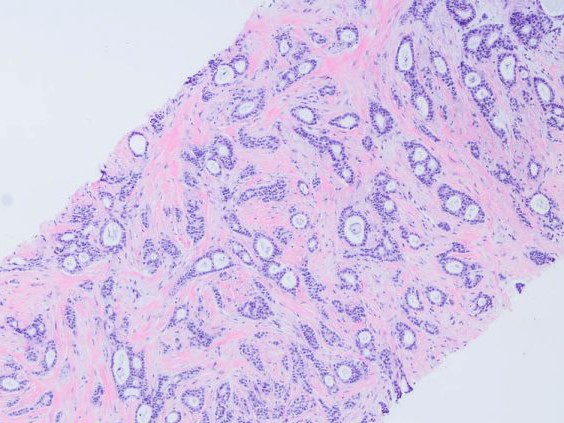

Microscopía de tumor de mama